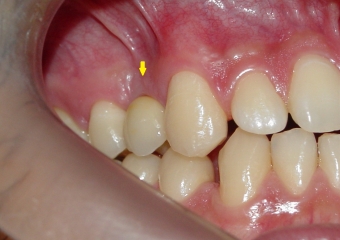

Clique nas imagens para ampliar